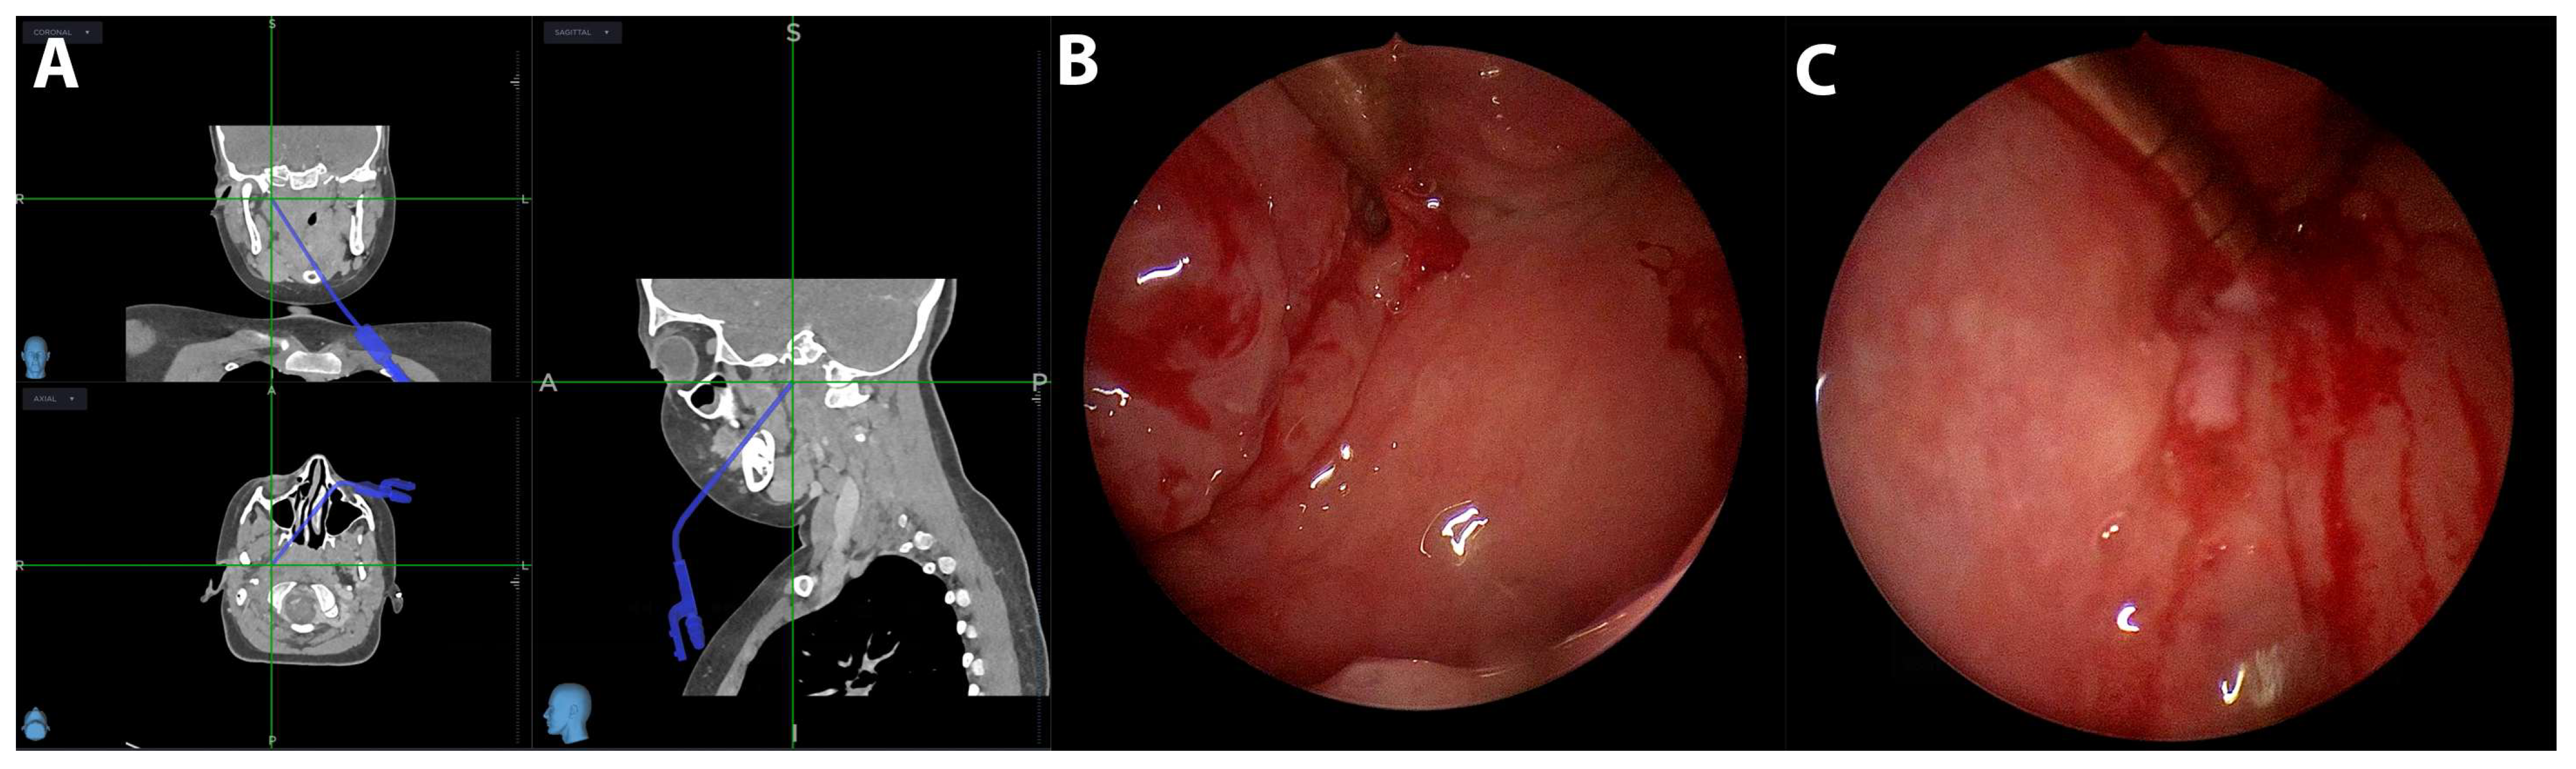

| 2 | 7 years | Parapharyngeal | Medial | Intubation | Transpharyngeal incision | Image guidance | H. aphrophilus | Clindamycin | 2 |

| 3 | 6 years | Parapharyngeal | Medial | Intubation | Transpharyngeal incision | Image guidance | S. pyogenes, S. oralis | Clindamycin, Ceftriaxone | 2 |